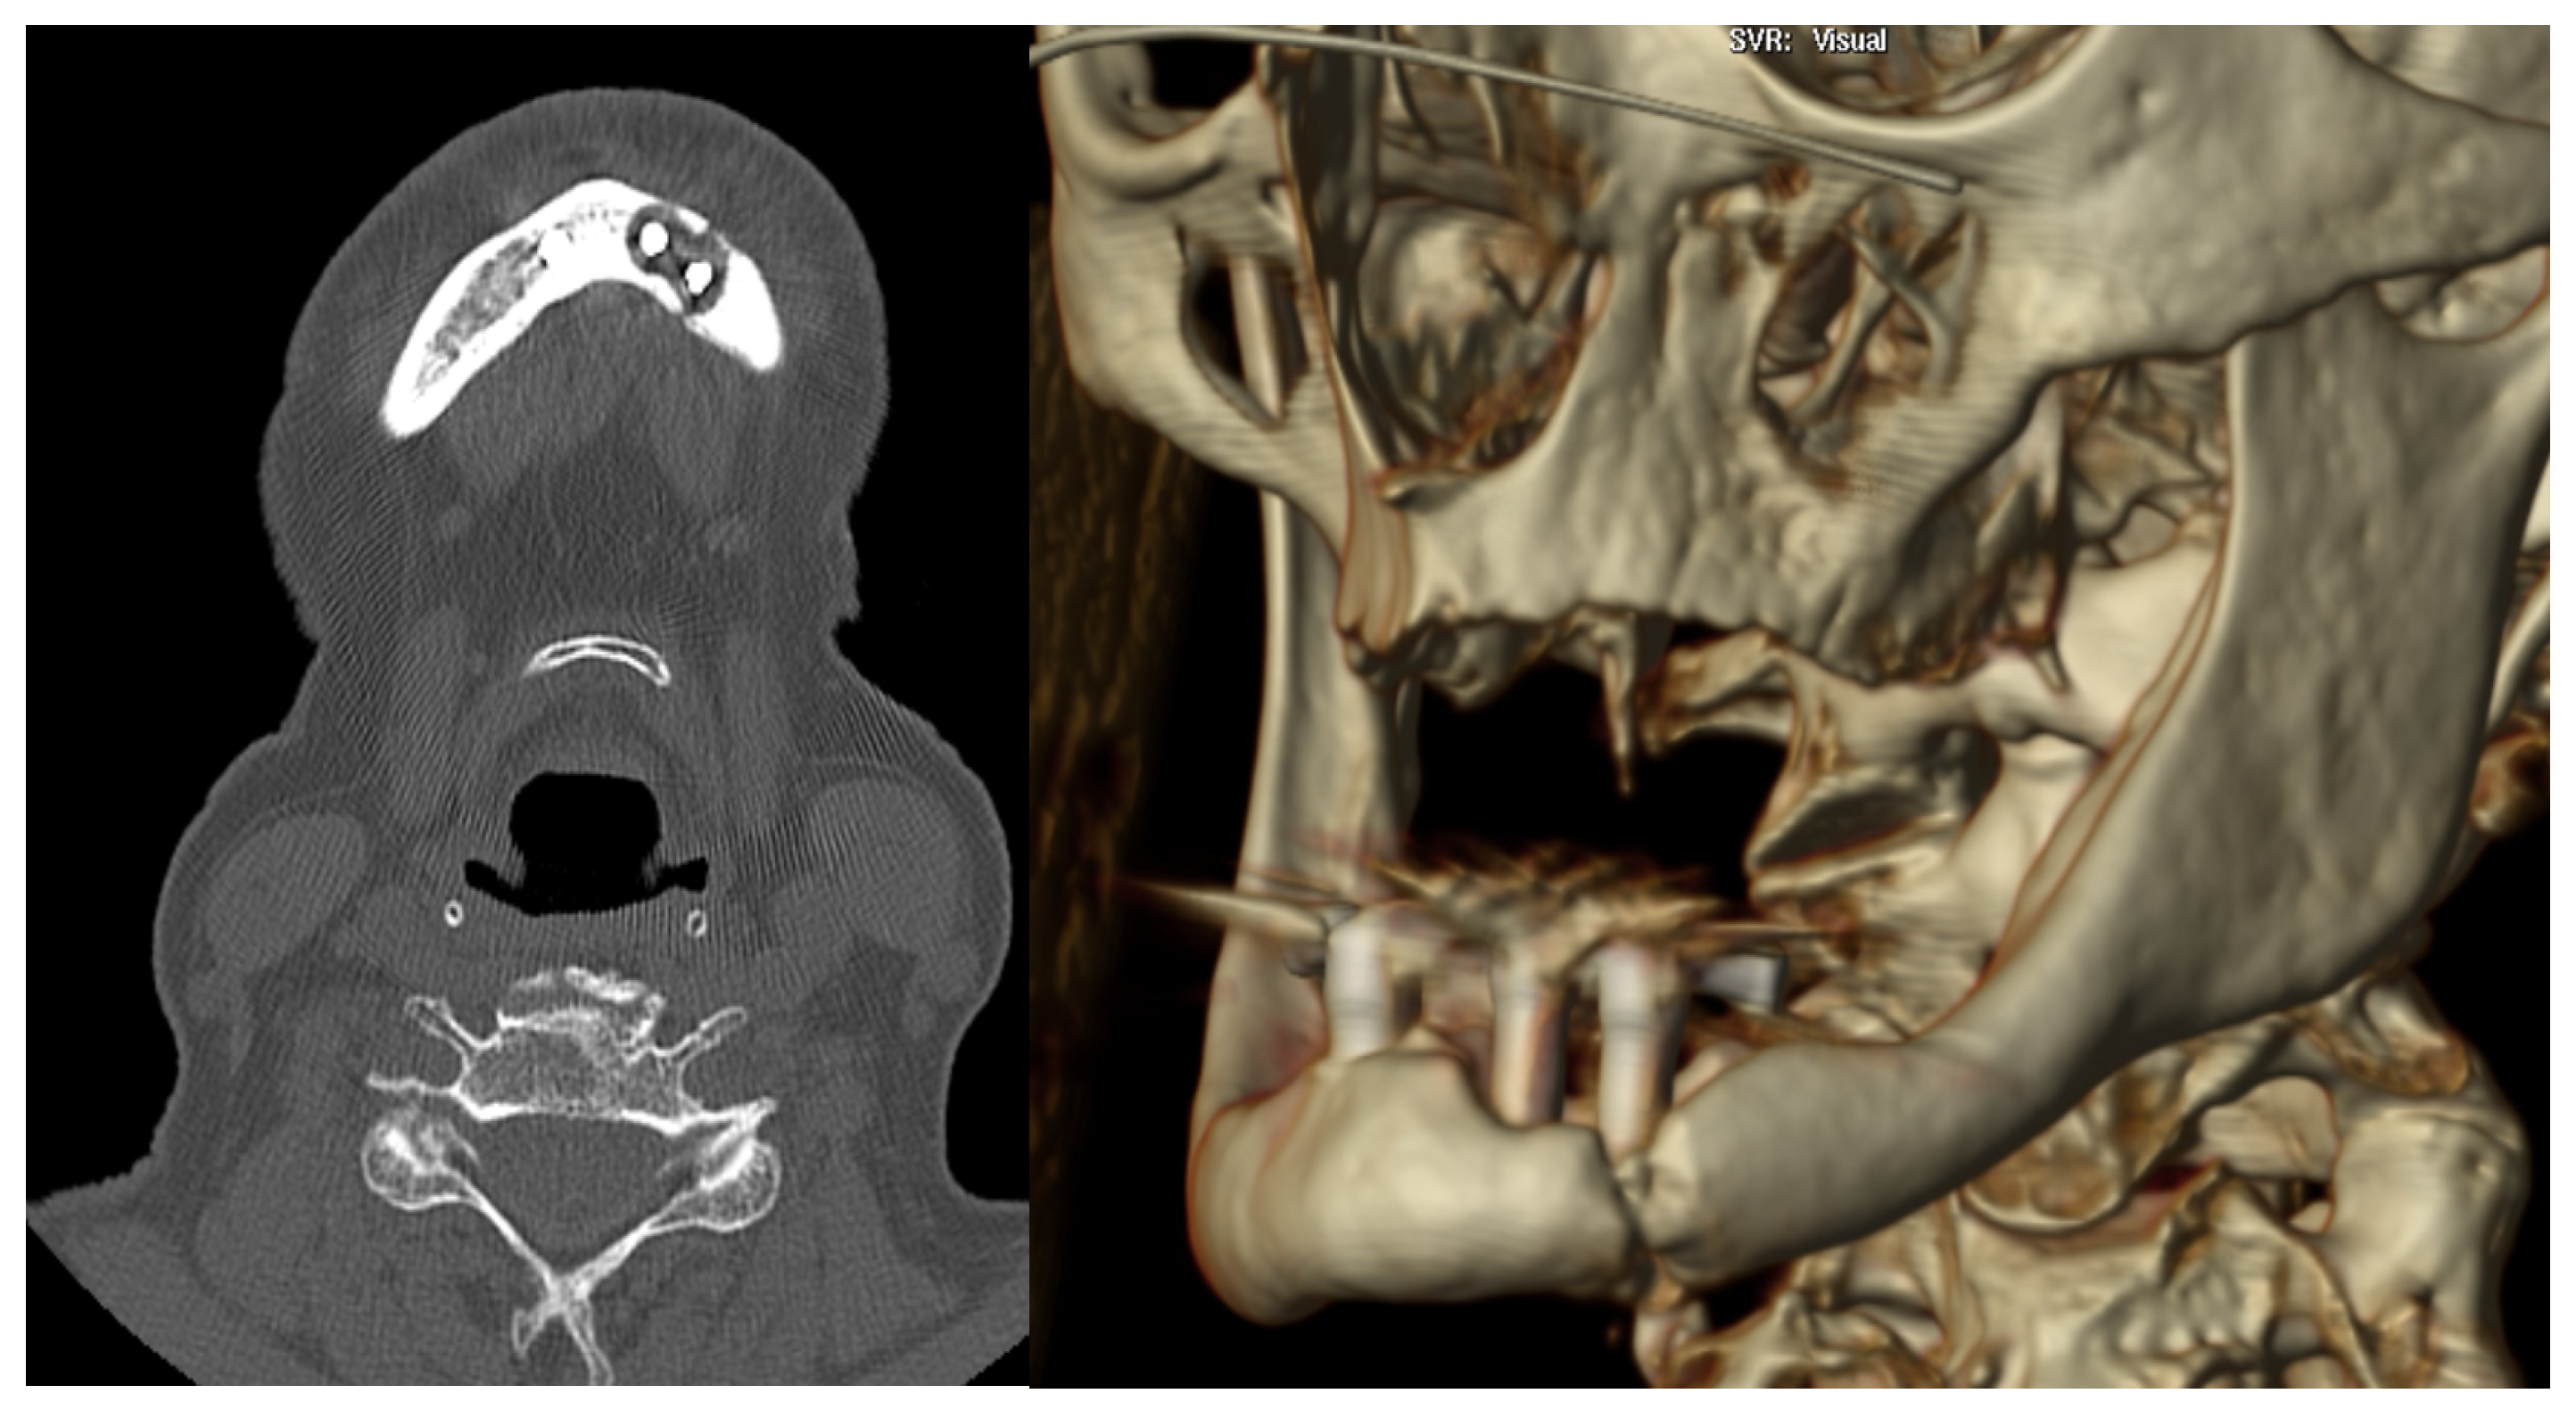

3.1. Case 1

3.2. Case 2

| Diagnostic imaging studies | Orthopantomography (OPG) | 6 (100%) |

| Computed tomography (TC) | 5 (83.3%) | |

| Location | Left parasymphyseal | 2 (33.3%) |

| Left body | 3 (50%) | |

| Bifocal (left body and right ramus) | 1 (16.67%) | |

| Fracture pattern | Simple | 5 (83.3%) |

| Bifocal | 1 (16.67%) | |